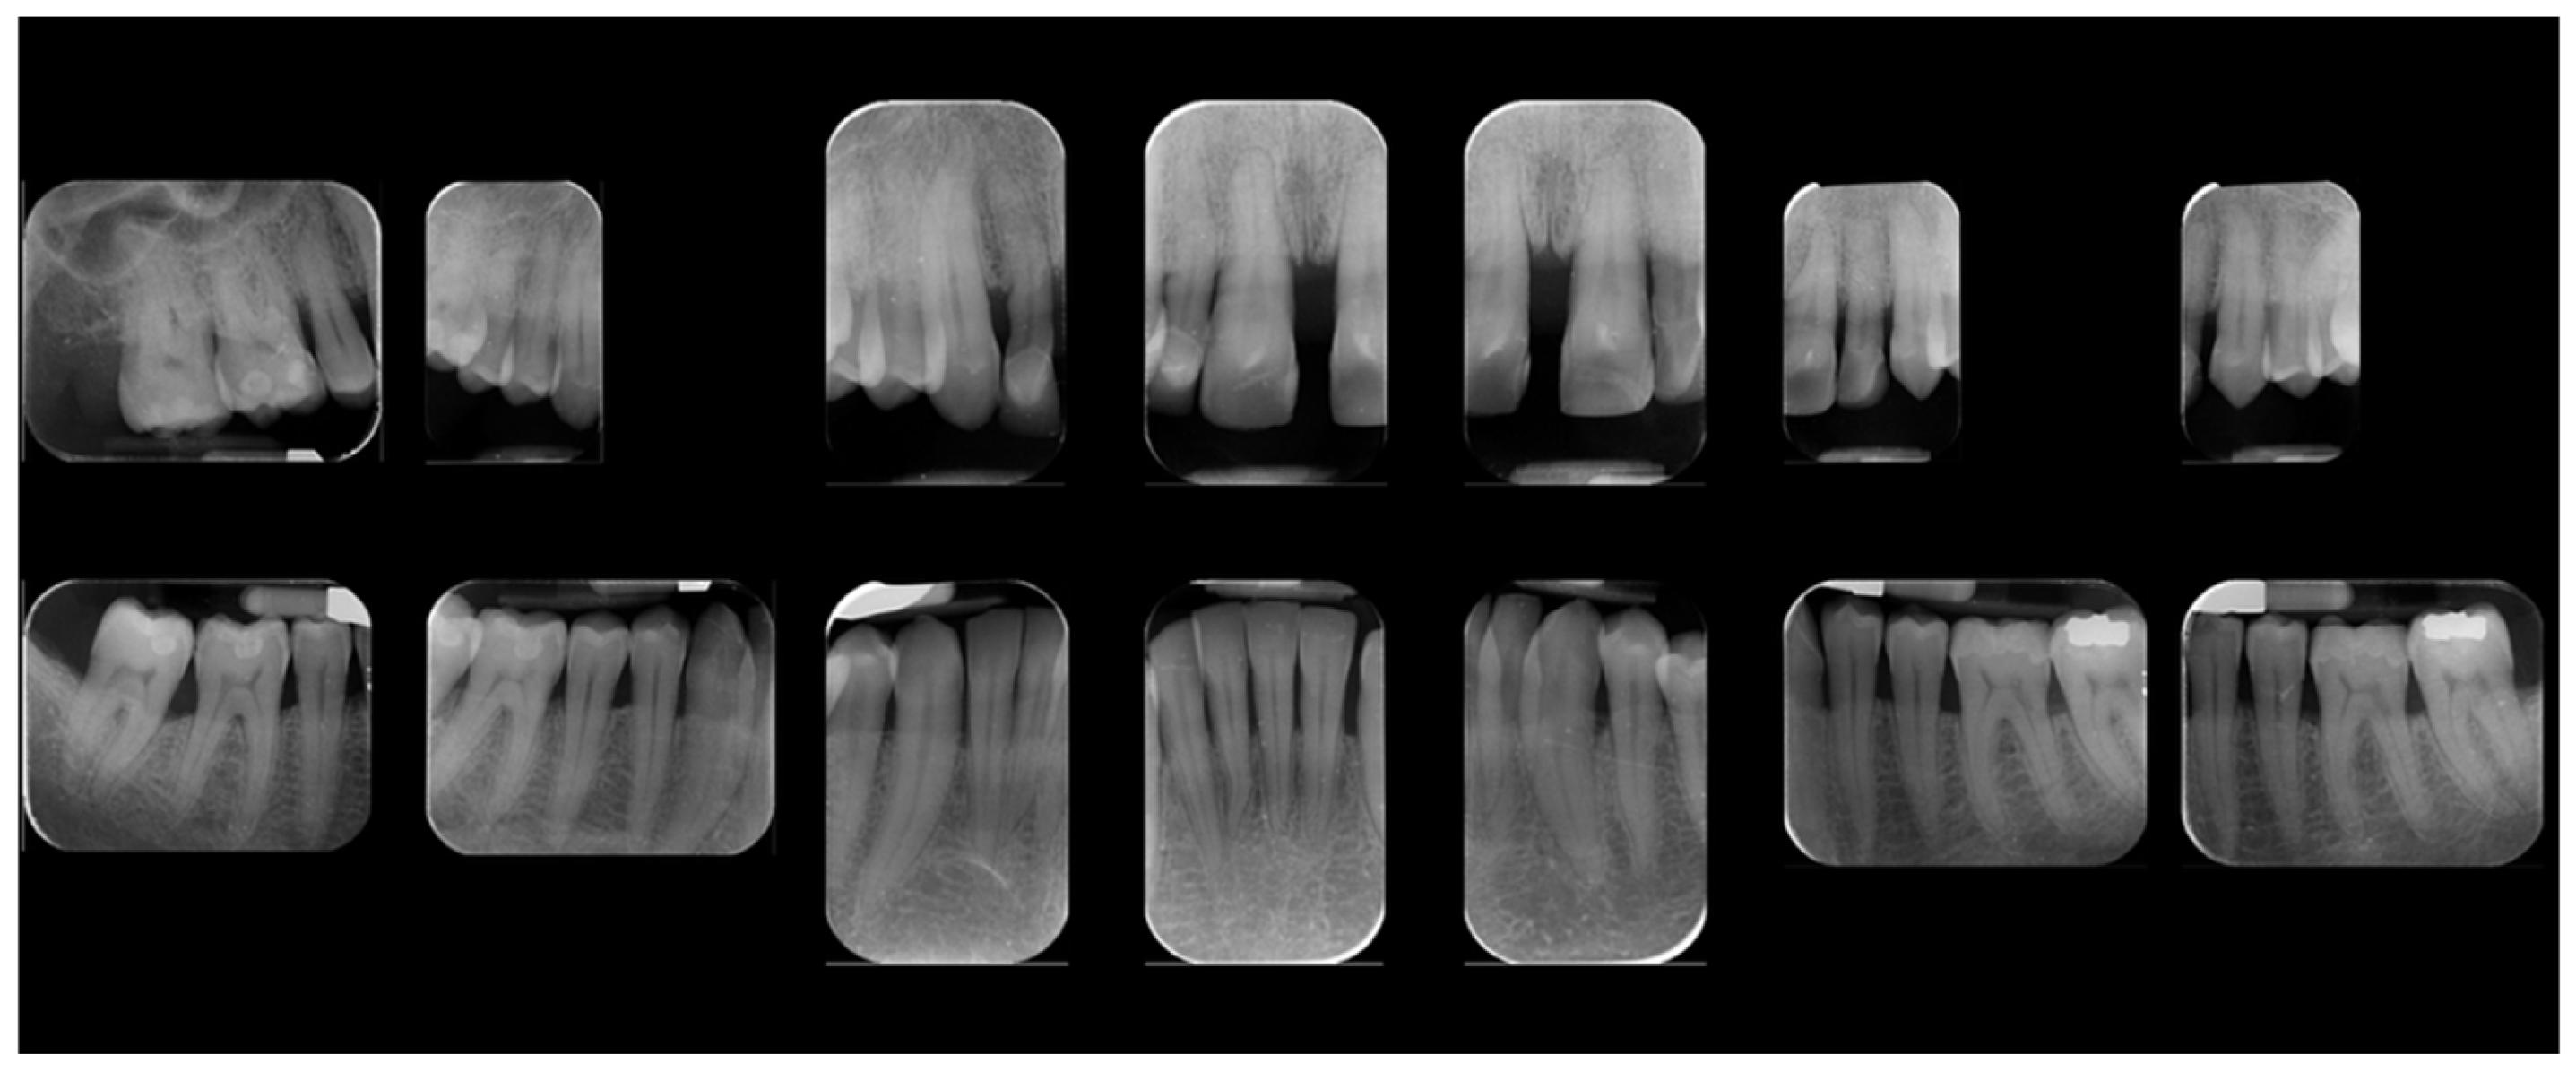

A 39-year-old male patient presented for prosthetic rehabilitation of the anterior maxillary region, primarily motivated by aesthetic concerns and periodontal health improvement. The patient reported a history of smoking (10–15 cigarettes per day since he was 18 years old) and had been diagnosed with localised stage III, grade B periodontitis. Even if the defect is mostly horizontal and localised to the II sextant, stage III was defined due to the bone loss extending to the middle third of the roots and the probing depth is ≥6 mm in this sextant. Moreover, smoking represents a risk factor able to classify the case as grade B. Initial clinical and radiographic evaluation (Figure 1) revealed the absence of all four third molars, the presence of conservative restorations on teeth 1.6, 3.7, and 4.6, and evidence of horizontal alveolar bone resorption in the regions corresponding to teeth 1.4 and 2.3. A conoid morphology was noted in the upper left lateral incisor.

Figure 1. Initial radiographic assessment.

The occlusal plane appeared canted relative to both the labial commissure and the horizontal reference plane, whereas the interpupillary line was centred. Functional analysis demonstrated a minor discrepancy between the centric relation and maximum intercuspation (0.5 mm), a deep bite, and group function occlusion. An evaluation of maxillary positioning, mandibular dynamics, and temporomandibular joint (TMJ) function was conducted using the Zebris Jaw Movement Analysis System (JMA, zebris Medical GmbH, 88316 Isny, Germany). Periodontal assessment at baseline revealed stage III, grade B periodontitis with a mean probing depth of 2.6 mm, mean sextant probing depth of 4.8 mm, clinical attachment loss averaging 2.2 mm, a plaque index of 12%, bleeding on probing at 16%, and grade I mobility of teeth 1.1, 1.2, 2.1, and 2.2 (Figure 6).

Figure 6. Initial periodontal examination. Red lines indicate the probing depth.